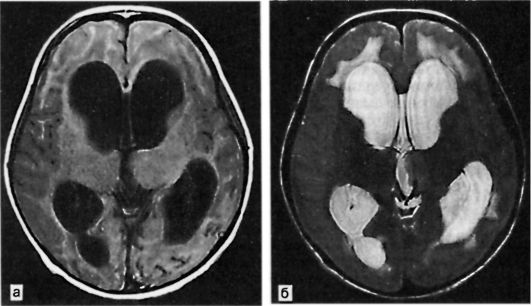

У детей старшего возраста и взрослых размеры и форма черепа при повышении внутричерепного давления не меняются в связи с прочным сращением черепных костей. Однако и в таких случаях при перкуссии черепа нередко можно выявить характерный для гидроцефалии симптом Мак-Кьюна. Наиболее демонстративна визуализация проявлений гидроцефалии при компьютерной томо- графии (КТ) и магнитно-резонансной томографии (МРТ) головы (рис. 20.2). Эти методы позволяют не только подтвердить наличие гидроцефалии, но и опре- делить степень выраженности расширения желудочковой системы, состояние субарахноидальных пространств и, таким образом, нередко позволяют судить о форме гидроцефалии и ее причине.

Рис. 20.2. МРТ головного мозга при гидроцефалии. а - в режиме Т1; б - в режиме Т2.